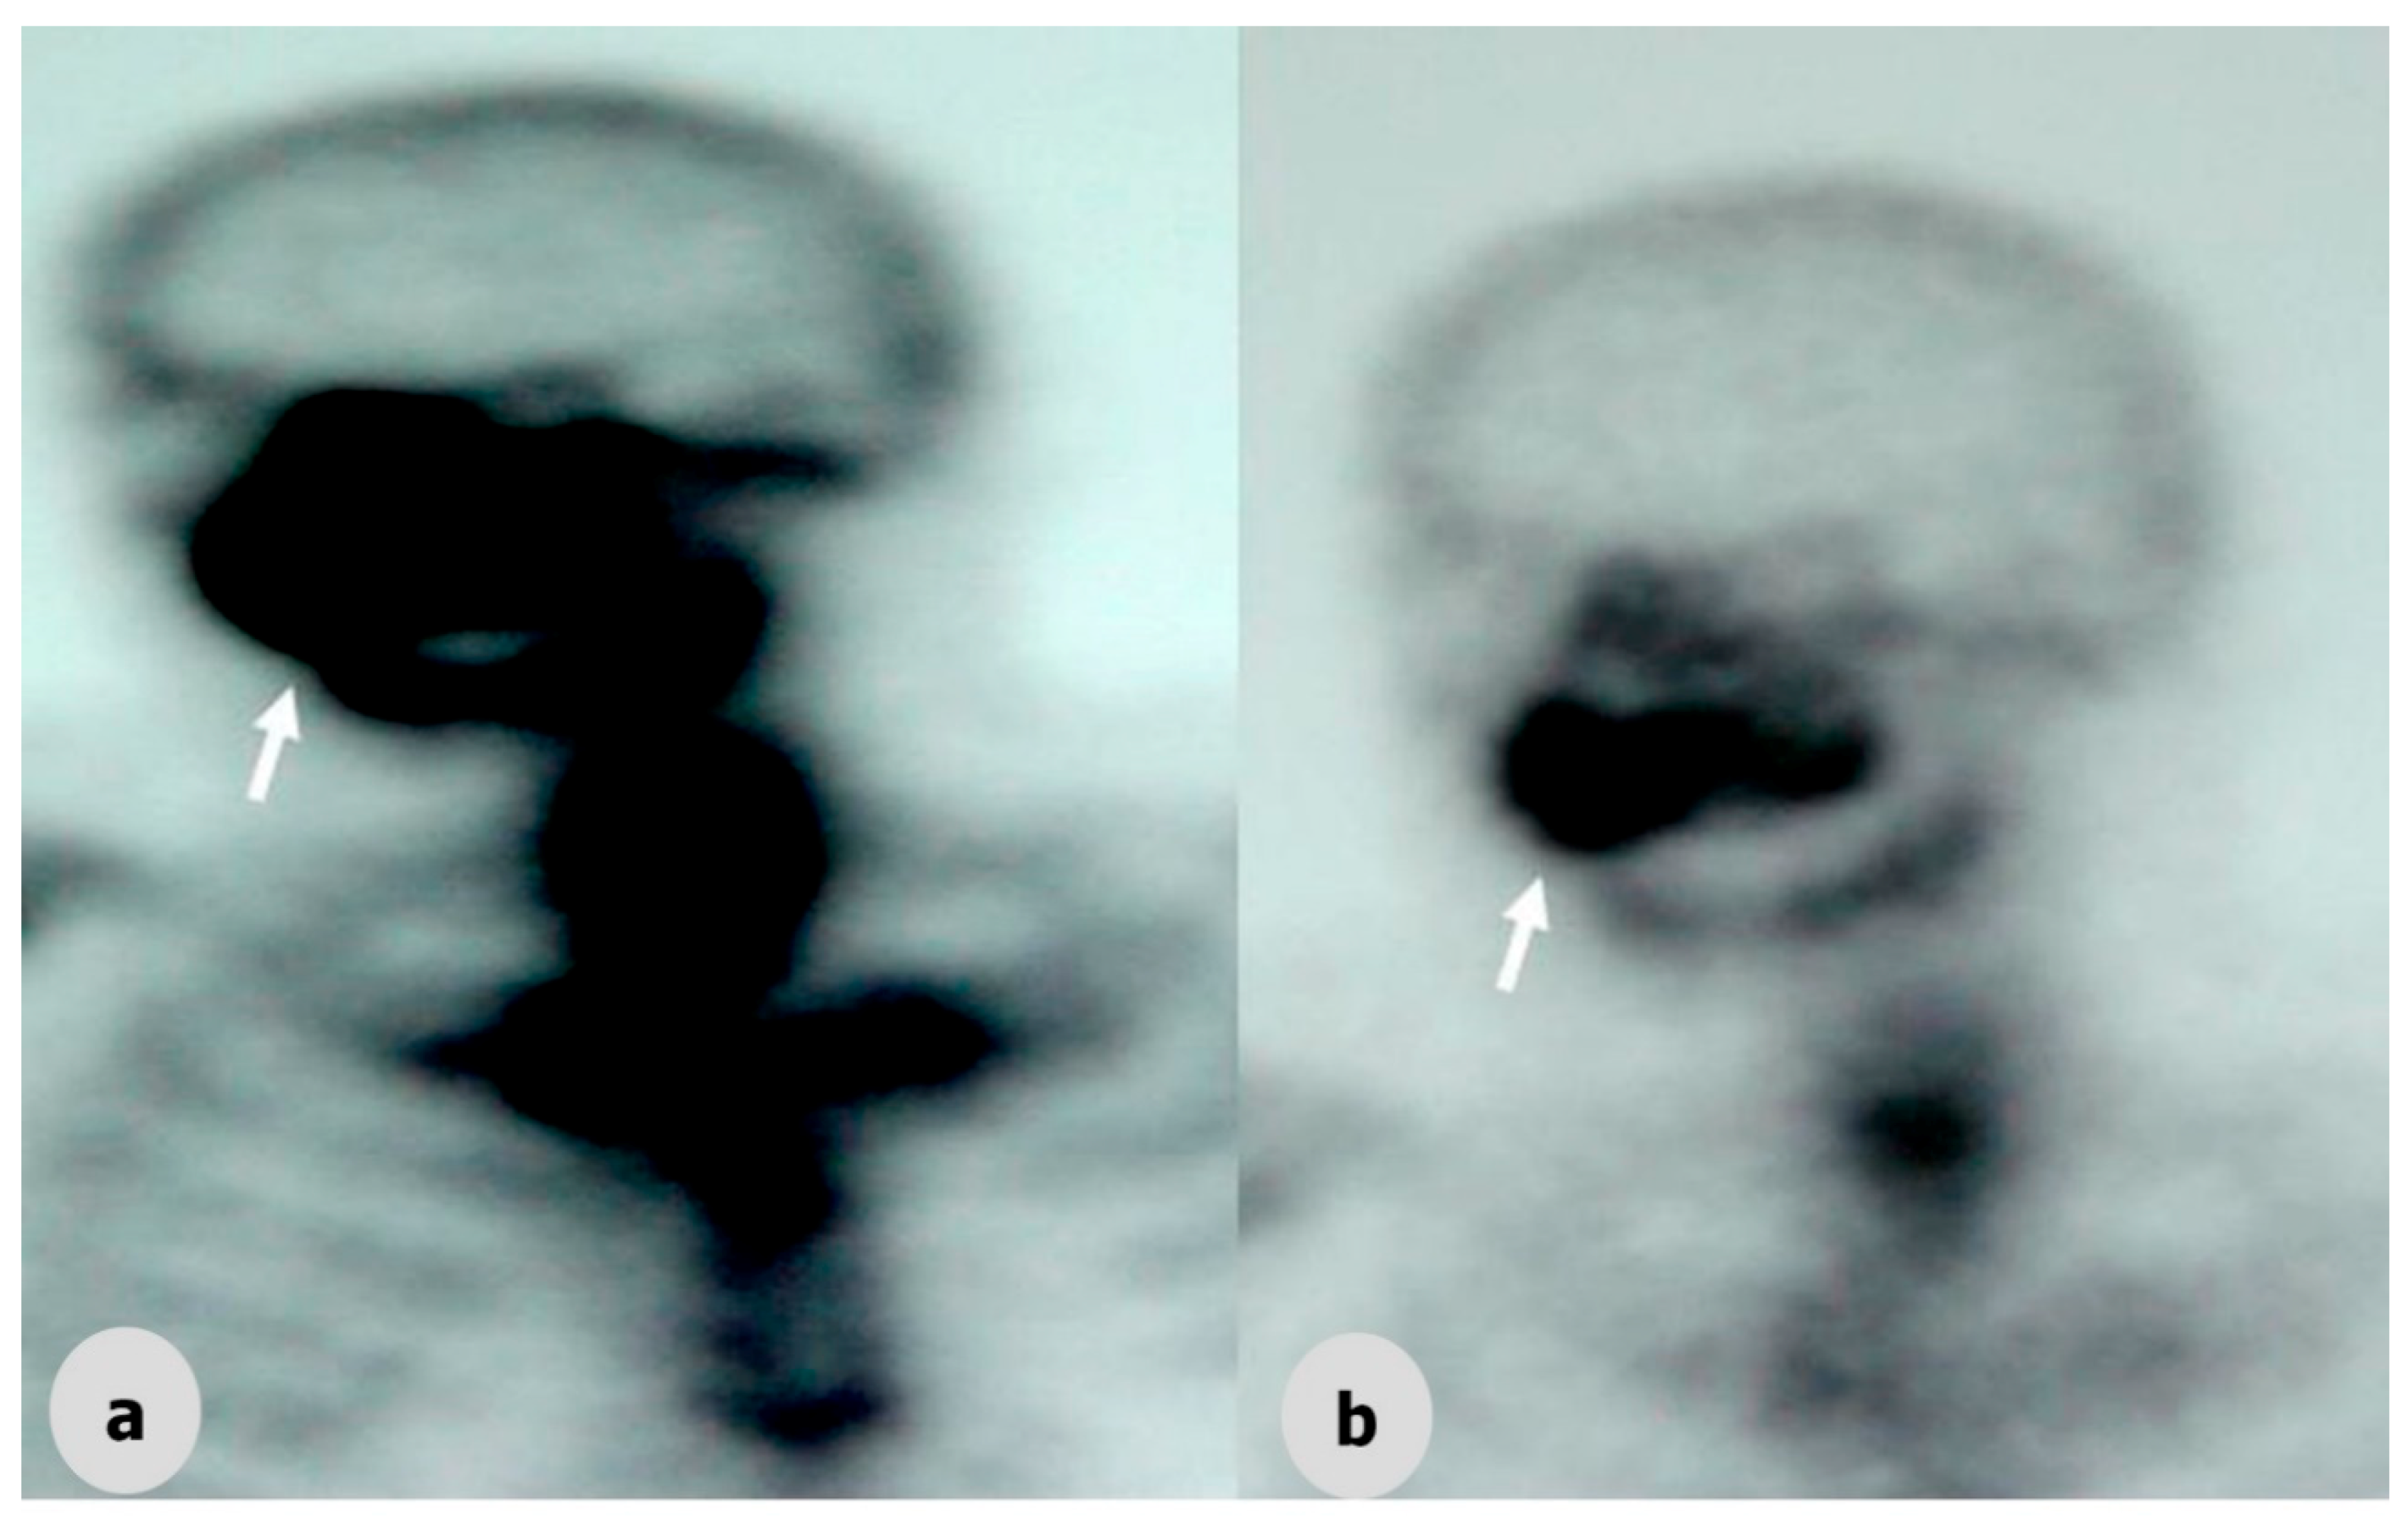

Figure 3. Scintigraphy images of a tumor (arrow) of the maxillofacial region before (a) and after (b) radiotherapy.